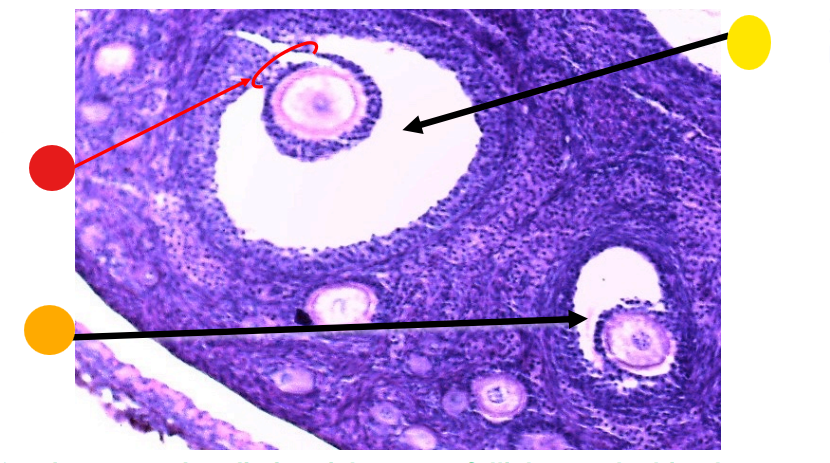

red

primordial follicles

red

primary follicles

red

tunica albuginea

orange

primary oocyte

yellow

primordial follicles

red

granulosa cells

orange

primary oocyte

what is this

primary follicle

red

granulosa cells

orange

thecal cells

yellow

zona pellucida

What is this

secondary follicle

what is this

secondary follicle

what is this

tertiary follicle

red

tunica albuginea

orange

primordial follicles

red

primary follicle

orange

secondary follicles

what is this

tertiary follicle